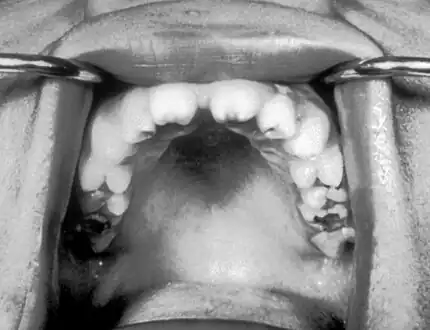

Late

Late onset features include deformity of the nose, lower legs, forehead, collar bone, jaw, and cheek bone.[1] Some of these bone defects can be detected early.[16] There may be a perforated or high arched palate, and recurrent joint disease.[1][4] Other late signs include scarred skin, intellectual disability, hydrocephalus, and juvenile general paresis.[1] Eighth nerve palsy, interstitial keratitis and small notched teeth may appear individually or together; known as Hutchinson triad.[1][18]

Late onset: Deformity of nose and palate

Hutchinson's teeth

Mulberry molar

Absent teeth

Perforation of palate

Perforated hard palate